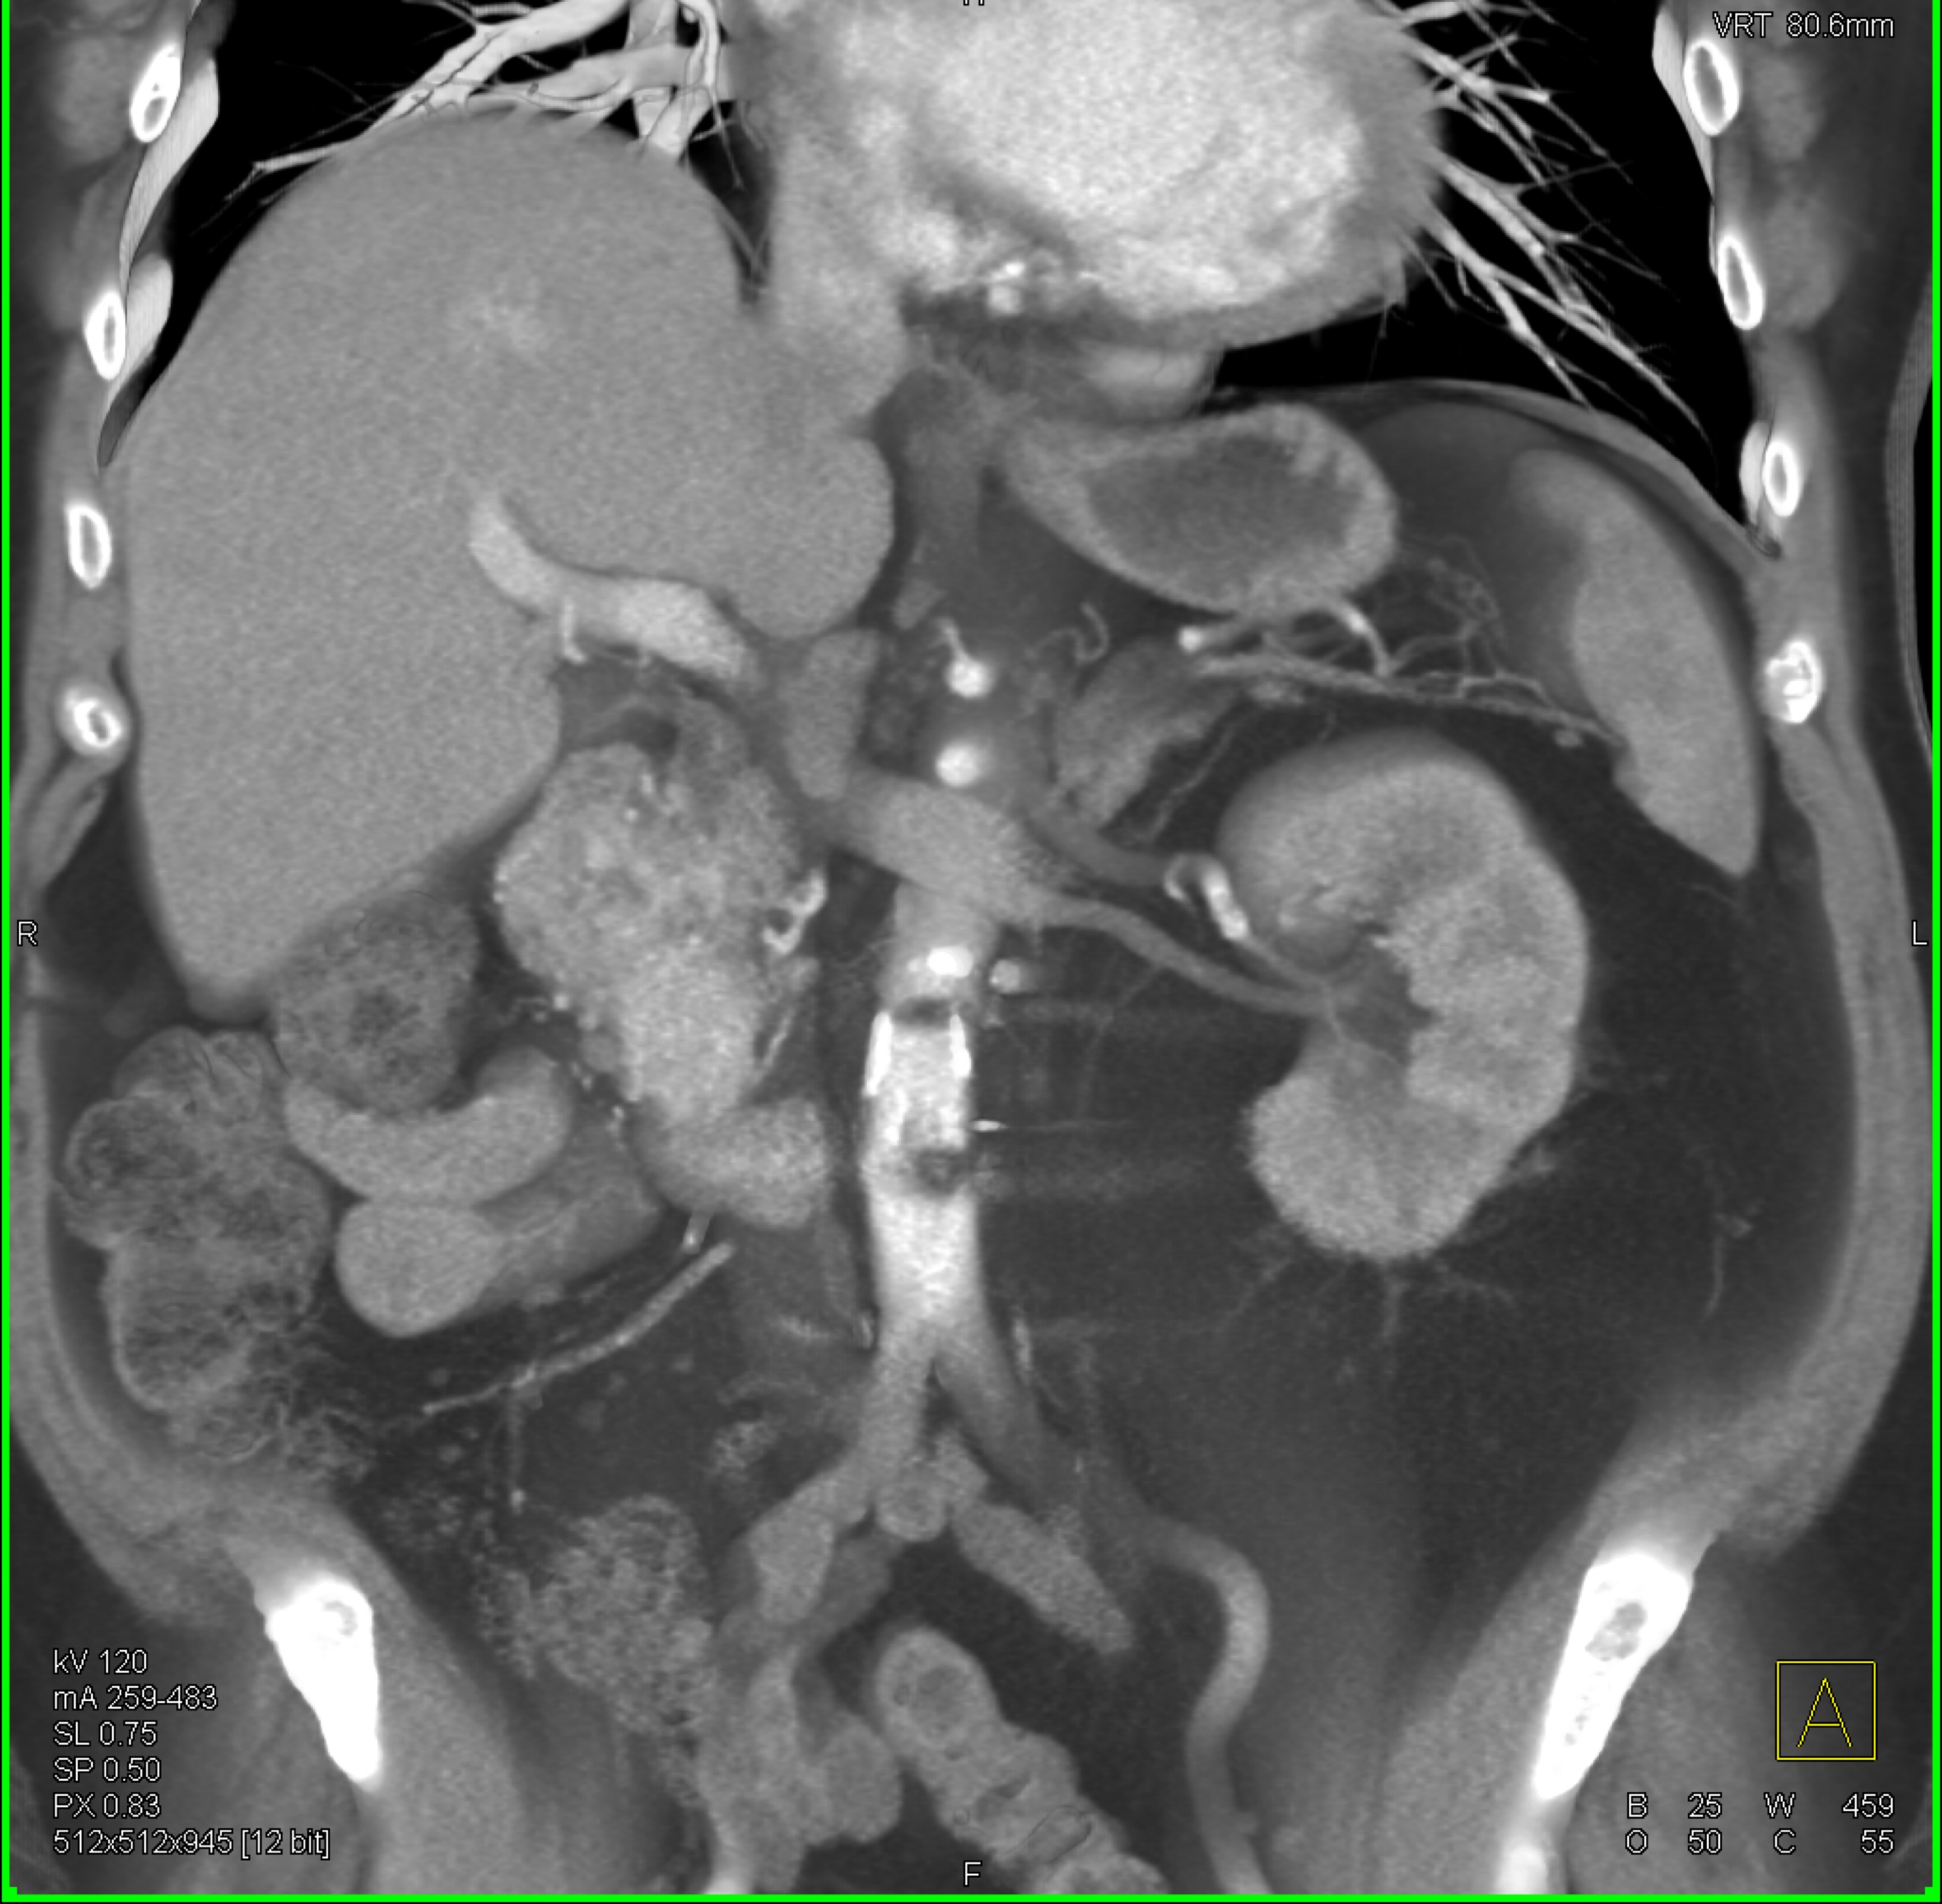

3) The most likely diagnosis in this case is?

adenocarcinoma

GIST tumor

carcinoid tumor

renal cell carcinoma metastatic to duodenum